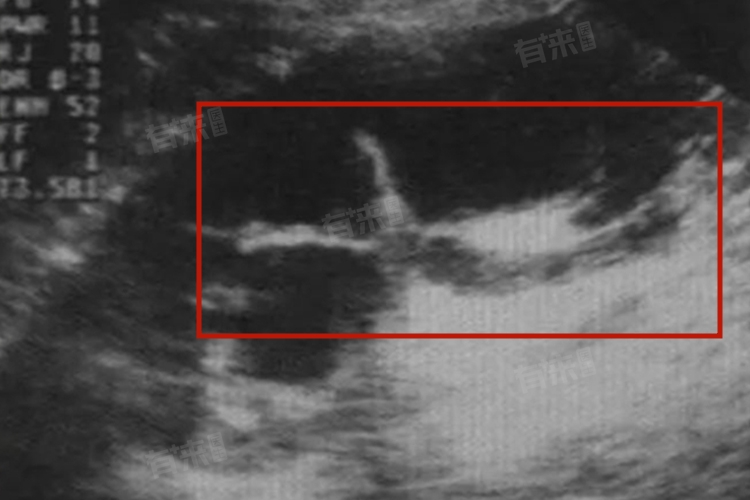

- 肾盂分离的宝宝在出生后可能会出现因尿路畸形、肾积水而引发的症状,如排尿困难、尿液带血丝、尿频、尿急等。如果肾积水严重,还可能在腹部触摸到包块,并伴有胀痛等症状。对于疑似双肾盂分离的胎儿,可以通过超声检查进行诊断。超声检查能够发现肾盂分离的情况,并测量肾实质的厚度,了解肾积水引起的肾实质萎缩情况。